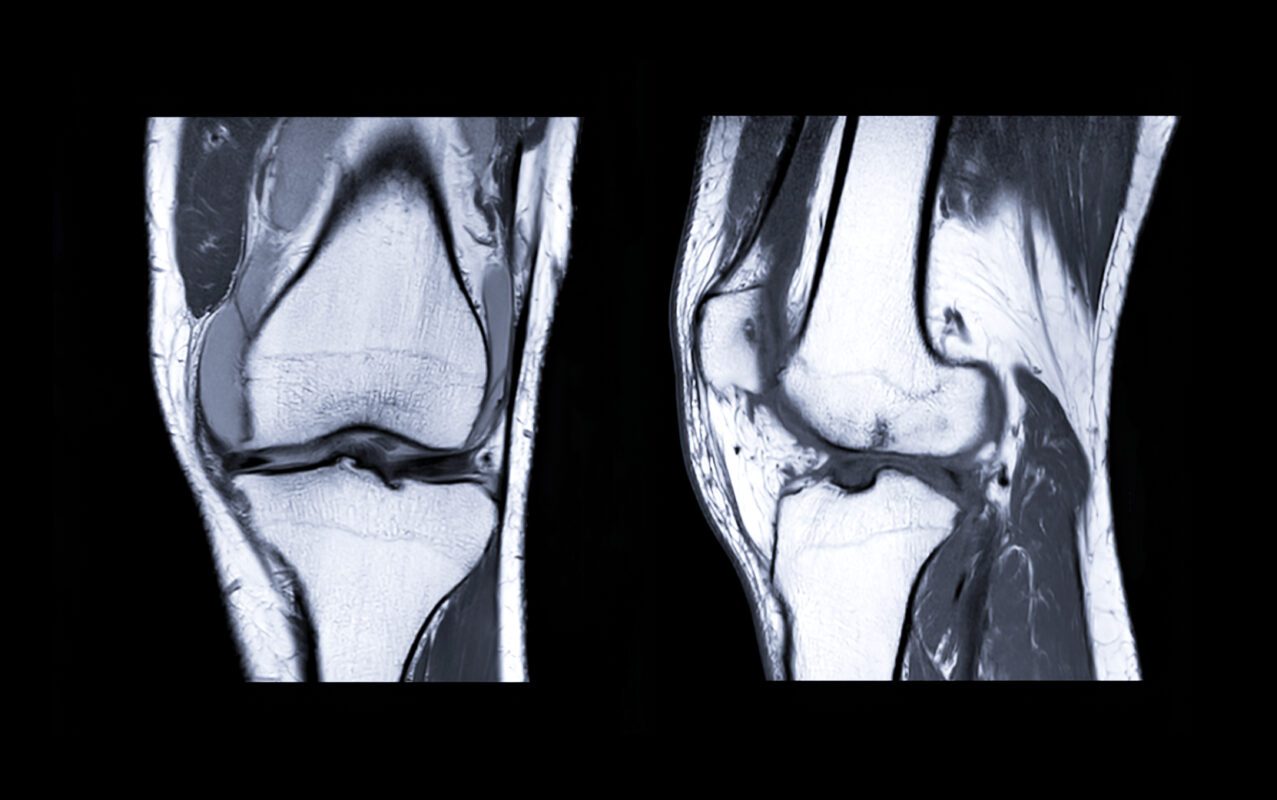

Bij het maken van een MRI-scan zijn er een aantal zaken waarop gelet moet worden. Belangrijk is dat er geen metalen voorwerpen in of op het lichaam zijn, zoals een pacemaker of metalen clips in het hoofd voor de behandeling van een aneurysma. De reden hiervoor is dat een MRI-scanner een zeer krachtige magneet bevat. Implantaten gemaakt van titanium zijn echter veilig in de MRI-scanner, omdat ze niet magnetisch zijn. Een MRI-scan produceert harde geluiden, wat sommige mensen als vervelend kunnen ervaren. Om dit te dempen, worden oordopjes of een koptelefoon verstrekt.

In sommige gevallen kan het nodig zijn om voor de MRI-scan een contrastmiddel te drinken. Hoewel dit zeldzaam is, kan het bij sommige mensen een allergische reactie veroorzaken, zoals misselijkheid, braken, waterige ontlasting en darmkramp.

Tot nu toe is er geen bewijs dat een MRI-scan schadelijk is voor het ongeboren kind. Desondanks is het belangrijk om zwangerschap of een vermoeden daarvan altijd aan de behandelend arts te melden voordat u een MRI-onderzoek ondergaat.